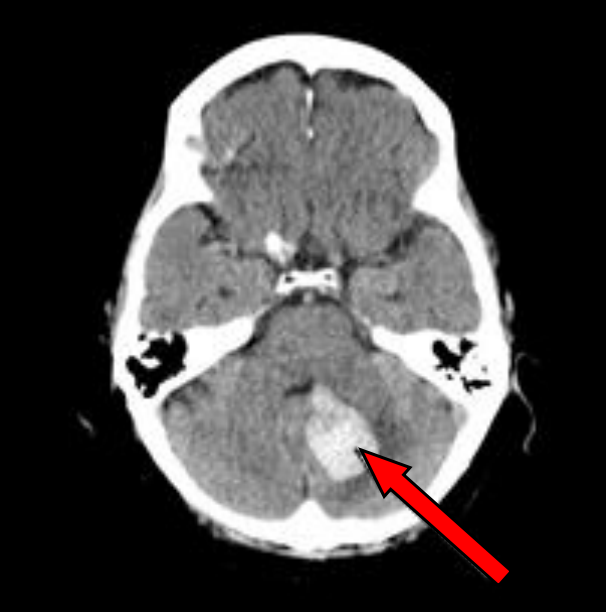

Na którym obrazie TK uwidoczniony jest artefakt spowodowany ruchami oddechowymi pacjenta?

A. Obraz 3

B. Obraz 2

C. Obraz 4

D. Obraz 1